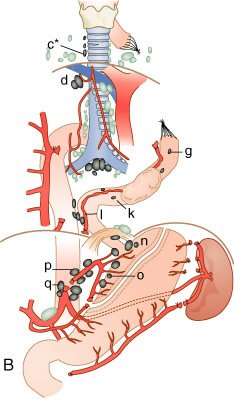

Mapa de linfonodos para câncer esofágico. A, Visão anterior. B, Visão lateral esquerda. C, Visão lateral direita. Estações ganglionares: l, supraclavicular; 2R, paratraqueal direito; 2L, paratraqueal esquerdo; 3P, mediastinal posterior; 4R, ângulo traqueobrônquico direito; 4L, traqueobrônquico esquerdo; 5, aortopulmonar; 6, mediastinal anterior; 7, subcarinal; 8M, paraesofagiano médio; 8L, paraesofagiano inferior; 9, ligamento pulmonar inferior; 10, hilar; 15, diafragmático; 16, paracardial; 17, gástrico esquerdo; 18, hepático comum; 19, esplénico; 20, celíaco A falta de serosa do esôfago tende a favorecer a extensão local do tumor.

A extensa drenagem linfática mediastinal, que se comunica com os vasos colaterais cervicais e abdominais, é responsável pelo achado de metástases ganglionar, mediastinal, supraclavicular ou do tronco celíaco em, pelo menos, 75% dos pacientes com carcinoma esofágico. Cânceres do esôfago cervical drenam para os linfonodos cervicais profundos, paraesofágicos, mediastinais posteriores e traqueobrônquicos. Os tumores do terço inferior disseminam para os linfonodos paraesofagianos, celíacos e do hilo esplénico. A disseminação a distância para fígado e pulmões é comum.

A) Extensão da ressecção e da dissecção ganglionar rotineiramente realizada para câncer do esôfago torácico. A porção mediastinal é a visão lateral. O brônquiofonte direito é afastado anteriormente. As letras a até r representam os grupos ganglionares mostrados abaixo

B) Dissecção menos extensa para câncer do esôfago torácico. As letras c até q representam os grupos ganglionares mostrados abaixo e* representa os linfonodos inferiores na cadeia do nervo laríngeo recorrente direito no pescoço e que podem ser removidos via toracotomia